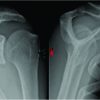

This is the case of a 64-year-old male mason who presented with left shoulder pain and disability. The patient underwent two procedures 10 months before presentation: a revision rotator cuff repair in his left shoulder and placement of a subacromial interpositional balloon spacer in his right shoulder. He continued to have significant pain in his left shoulder and felt a discrepancy between his two shoulders in terms of strength and function, favoring the right side. He presented for a discussion of options regarding treatment for his left shoulder. He denied any traumatic incident since his last procedures. He is taking opioid medication to control his shoulder pain. He has a history of hypertension and hypercholesterolemia, along with a surgical history that included a cerebral bypass and a cardiac stent placement procedure, for which he takes aspirin and ticagrelor. He also had a recent hemithyroidectomy for a thyroid cyst with an uneventful post-operative course. The patient has no history of inflammatory or rheumatologic diseases. He has a strong build with a height of 185 cm and weight of 101 kg. On physical examination, the patient demonstrated good cervical spine mobility with only mild limitations. The left shoulder showed well healing scars from his previous procedure, with mild muscular atrophy. Range of motion testing showed 140° of forward elevation, 90° of abduction, 30° of external rotation, and passive internal rotation reaching upper lumbar spine. Strength testing showed a score of 5 on forward elevation, 4+ on external rotation, and 5 on internal rotation. The patient had a negative belly press test and was neurovascularly intact. The patient rated his right shoulder to be in a significantly better state than his left shoulder and contemplated the possibility of undergoing a subacromial balloon placement in his left side as well to treat his pain. Magnetic resonance imaging (MRI) of the left shoulder demonstrated a large retear of the previously repaired rotator cuff, mainly at the supraspinatus tendon and extending into his infraspinatus tendon (Fig. 1).

Sagittal MRI views showed severe atrophy of infraspinatus (Fig. 2) His subscapularis appeared intact and the patient displayed low/intermediate grade arthritic changes.